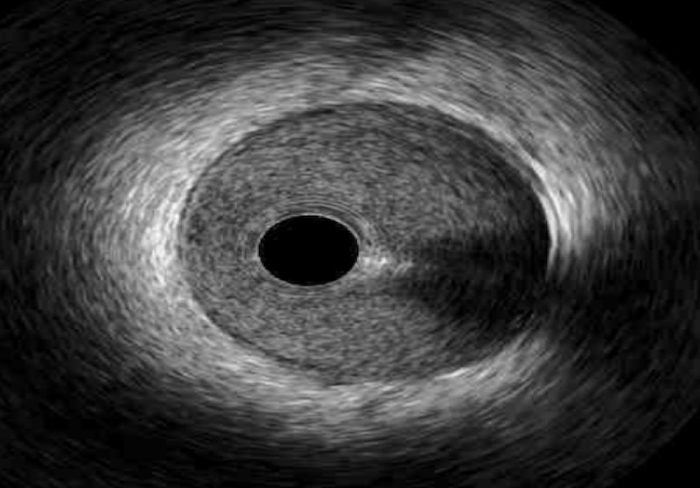

The main modalities of ICI (IVUS and OCT) differ significantly in their

mechanisms (Table 1). While IVUS utilizes ultrasound waves formed by the

oscillatory movement of a transducer as the source of image production [6], OCT

utilizes near-infrared light for intracoronary visualization, creating a

bloodless field by high velocity contrast injection for rapid lumen imaging

acquisition. Contemporary iterations of OCT now utilize frequency domain (FD)

imaging which utilizes high viscosity liquids to the same end [7, 8]. Coronary

angiography is generally required for both imaging modalities. For coronary

artery access with IVUS, a transducer is attached to a guide catheter (a minimum

of 5 Fr) and luminal measurements are obtained by manual or motorized pullback

upon vessel entry [8]. The axial and lateral resolution of greyscale IVUS is

100–150

| Modality: | OCT | IVUS |

| Mechanism: | near-infrared light | ultrasound waves |

| Penetration: | 2 mm | 4–8 mm |

| Resolution: | 10–20 mm (axial) | 100–150 mm (axial) |

| 20 mm (lateral) | 200 mm (lateral) | |

| Advantages: | plaque characteristics | vessel wall remodeling |

| stent changes, post-PCI | calcifications | |

| Limitations: | requires a bloodless field | discernment of layers of coronary vessel wall |

| Image acquisition (normal coronary vessel anatomy shown): |  |

|

The differences in penetration and resolution explain the inherent limitations

of both modalities in comparison. Given its relative limited resolution, IVUS is

unable to evaluate the separation of the vessel wall layers (i.e., intima, media

and adventitia) compared to OCT [10]. Therefore, OCT is better served within

reasonable penetration (